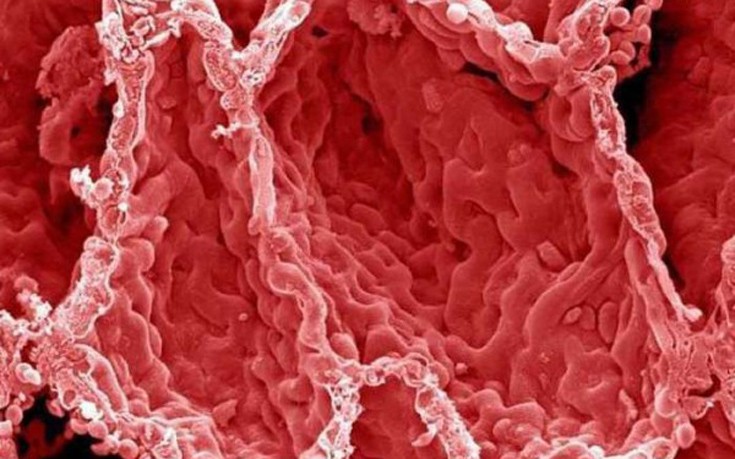

Αιμοπετάλια